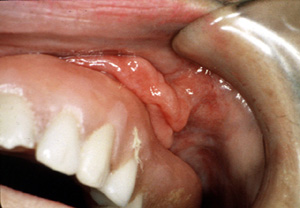

Con la dentadura postiza en el lugar, la pestaña encaja muy bien en la ranura con una porción de la lesión localizada debajo de la dentadura postiza y la mitad queda en la superficie externa.

Este épulis fisurado  involucra el vestíbulo de la mandibula anterior. Aunque no esté la dentadura postiza que produce dicha lesión, hace pensar en una asociación íntima entre la prótesis desaptada y la lesión. Los rasgos clínicos también hacen pensar en la posibilidad de malignidad. En todos los casos, se indica una biopsia para el diagnóstico preciso.